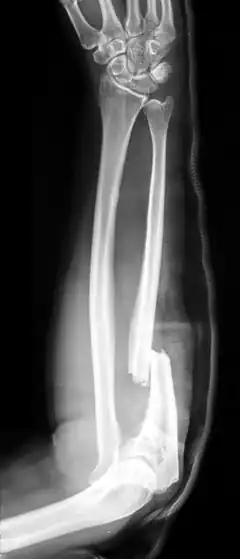

A fratura de Monteggia é uma fratura da ulna que afeta a articulação com o rádio. Mais precisamente, é uma fratura do terço proximal da ulna com deslocamento da cabeça do rádio.

Na criança geralmente é indicada terapia conservadora, que consiste em redução fechada e imobilização. Em adultos, a fratura geralmente é tratada cirurgicamente, com redução aberta e fixação interna.